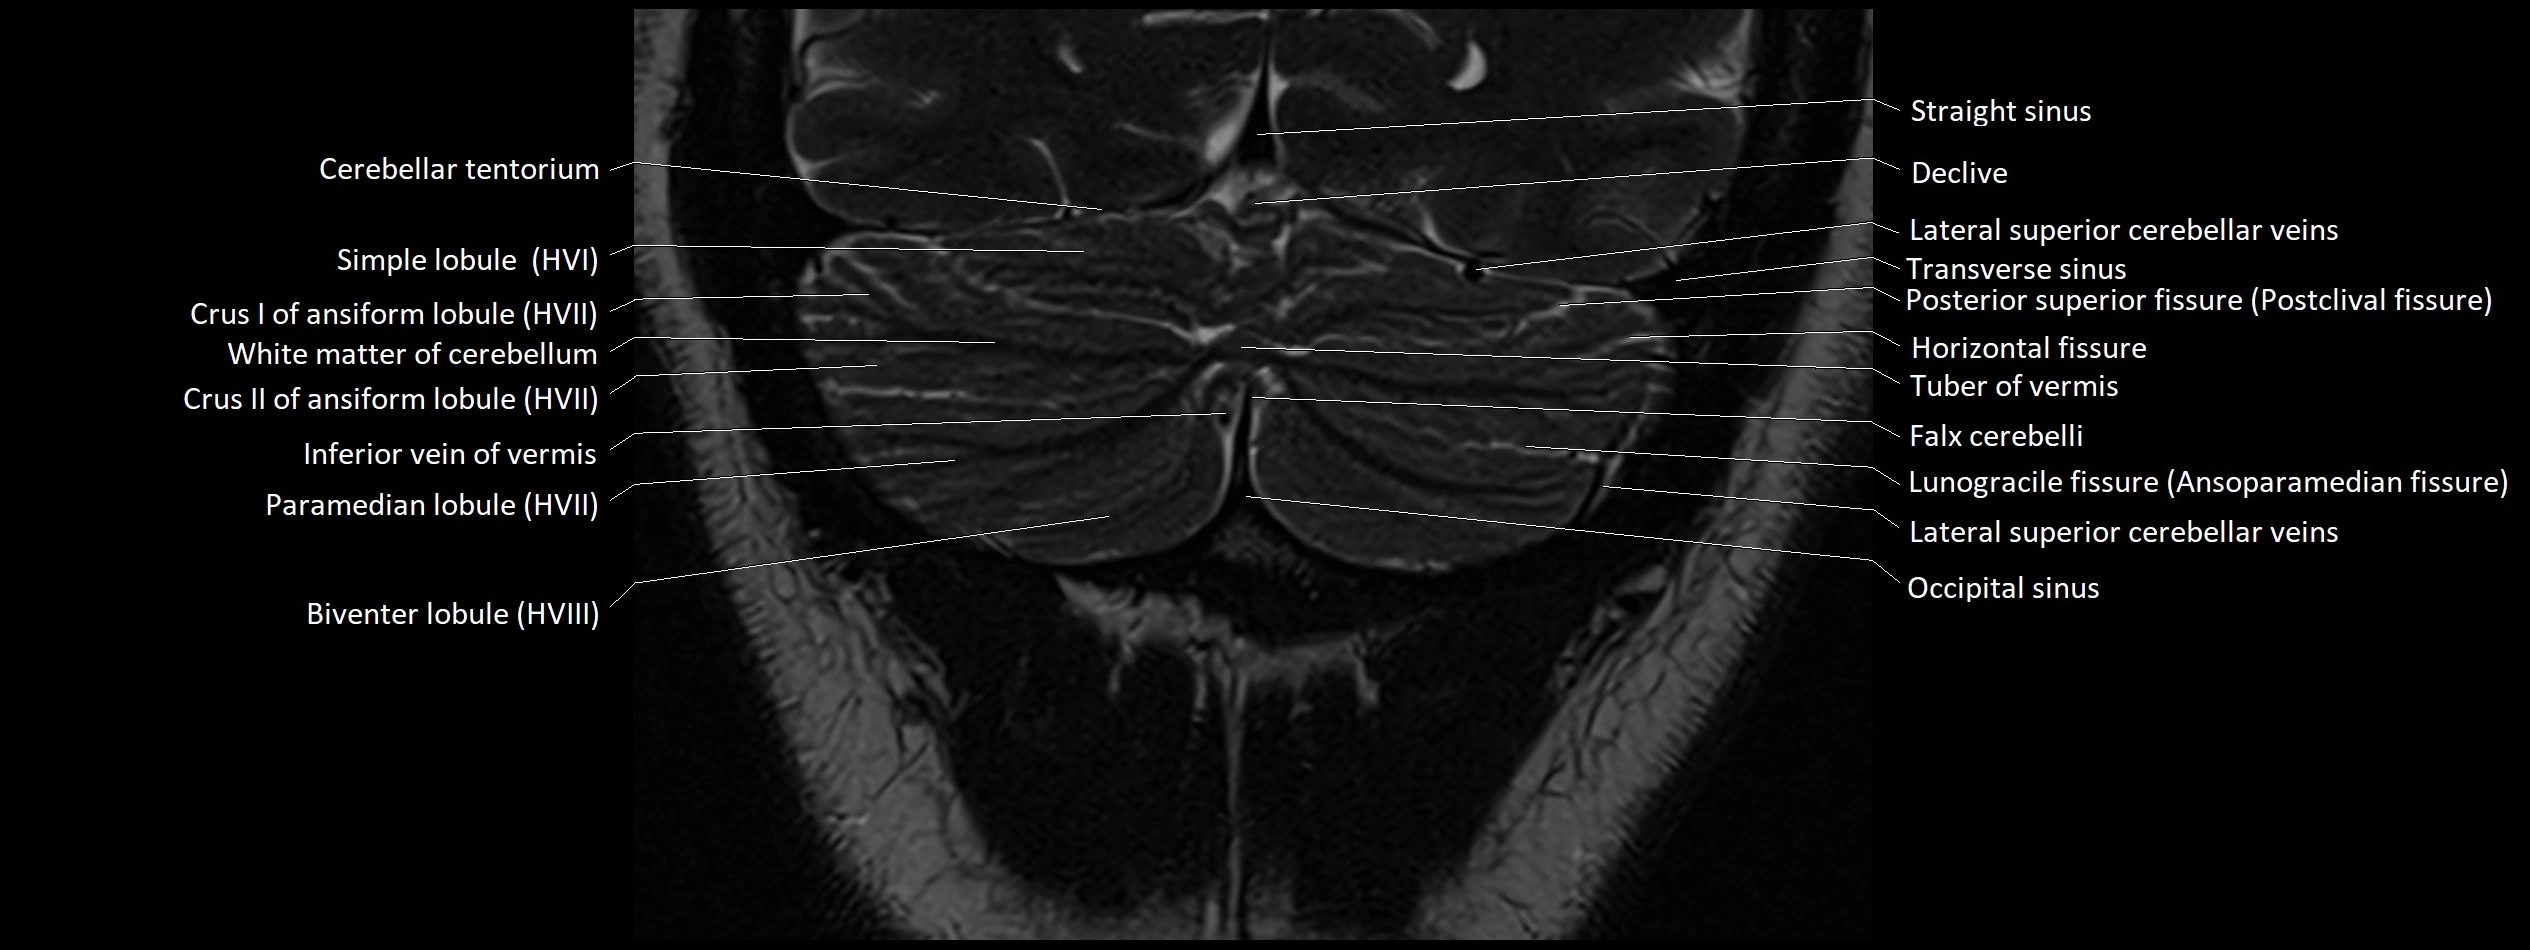

MRI images